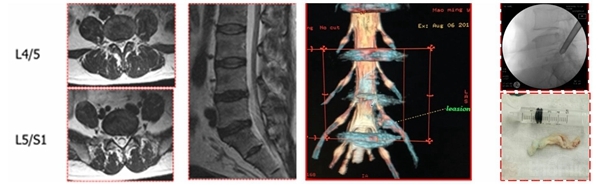

3D-CT:可观察骨性结构狭窄,如椎间孔区域狭窄,此类患者可行脊柱内镜下椎间孔扩大出口神经根减压治疗

3D-MRI:普通MRI无异常,3D-MRI发现游离髓核,行脊柱内镜取出游离髓核

3D-MRI:对一些特殊类型的椎间盘突出(如极外侧腰椎间盘突出)可起到更加准确的诊断作用